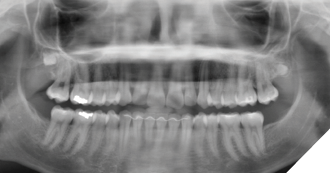

At the next follow-up one year later (18 years of age) the right maxillary supernumerary was relatively unchanged in position; however, a new supernumerary fourth molar was identified in the left posterior maxilla (Fig. 4).

Fig. 4